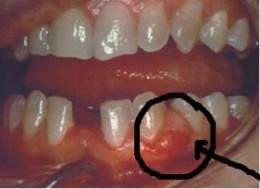

Absceso gingival

Absceso gingival. Es una inflamación purulenta localizada en la encía, que puede presentarse tanto en individuos sanos como afectados por enfermedad periodontal.

Es de aparición rápida, se presenta como un aumento de volumen localizado en la papila o la encía marginal, de forma redondeada u ovoide de superficie tensa y lisa y color rojo brillante. La lesión es dolorosa y los dientes vecinos pueden tener sensibilidad a la percusión. De no recibir tratamiento la lesión entre las 24 y 48 horas se hace fluctuante y puntiaguda, pudiendo aparecer un orificio en la superficie por donde drena el exudado purulento. Generalmente no se producen alteraciones sistémicas.